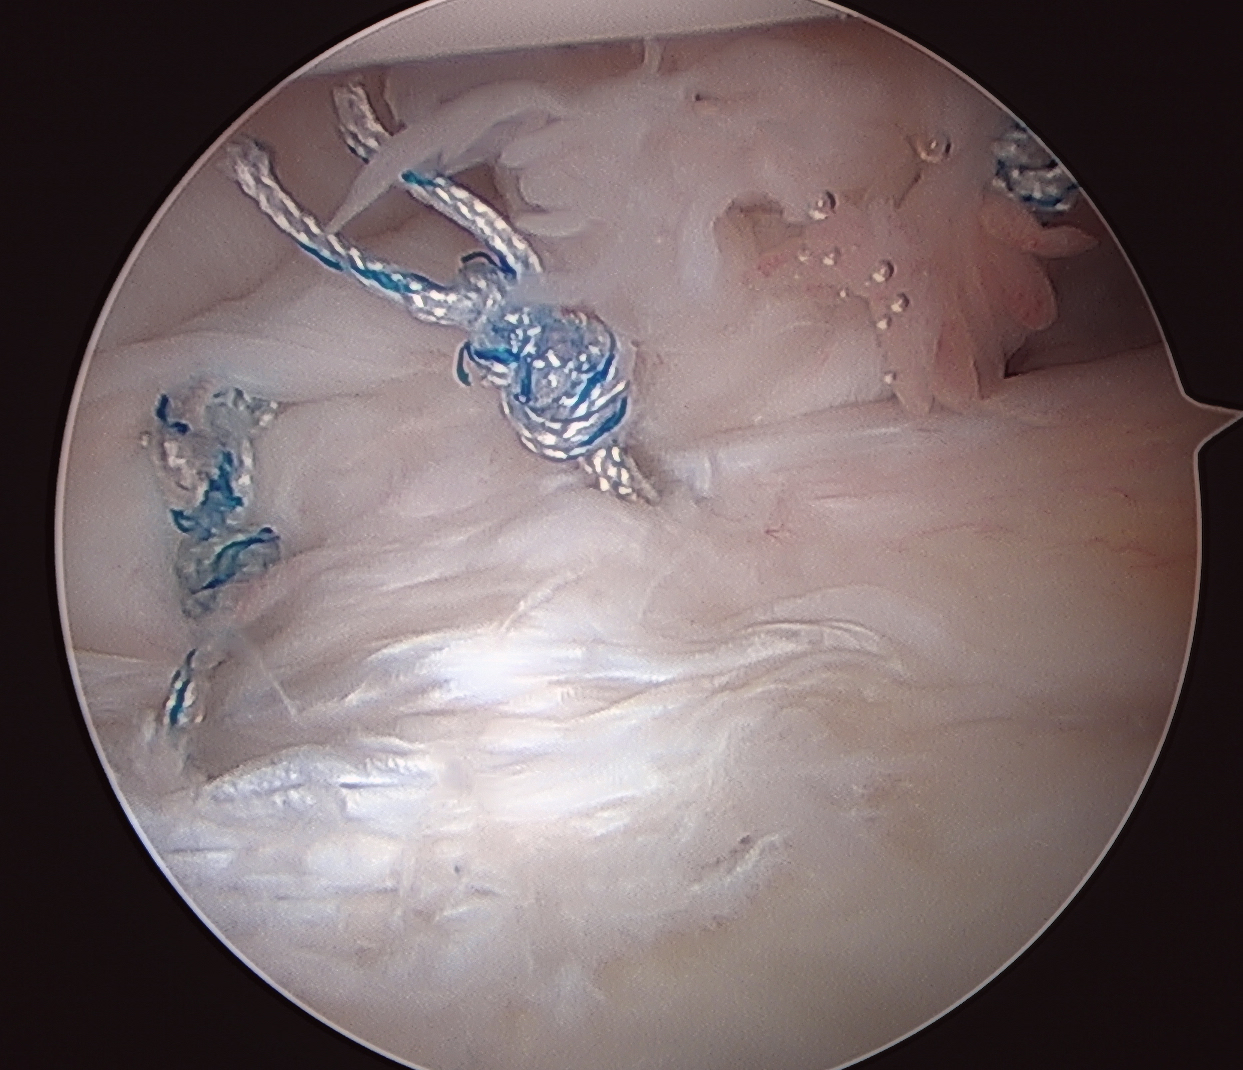

Side to side suture repair +/- HAGL repair

Side to side repair of capsular tear

Technique

- reduce capsule volume with sutures

- capsulorraphy

- can tie sutures to labrum

- can insert glenoid anchors to advance capsule